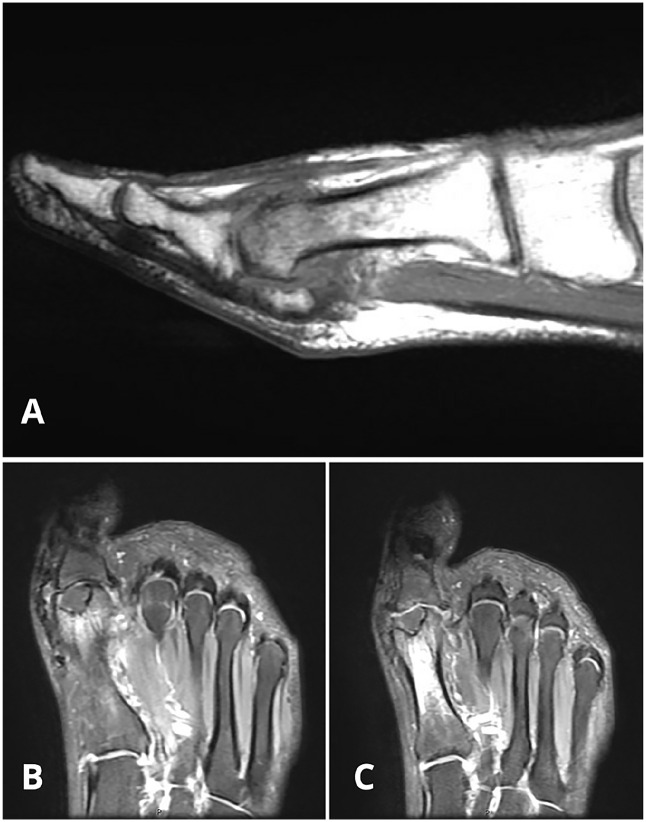

Methods: We report the case of a 43-year-old woman with persistent pain and functional limitations after a failed PVA hydrogel implant in the first MTP joint. The revision surgery involved a biologic resurfacing using the Osteochondral Autograft Transfer System (OATS) with a graft harvested from the ipsilateral femoral condyle, complemented by interpositional arthroplasty with a dermal graft and a proximal phalanx closing wedge osteotomy to correct residual hallux valgus.

Results: At the 3-year follow-up, the patient-reported complete resolution of pain and returned to full activity with improved range of motion (40 degrees dorsiflexion, 15 degrees plantarflexion). Radiographic evaluation demonstrated graft incorporation and restoration of joint space, confirming the success of the procedure.